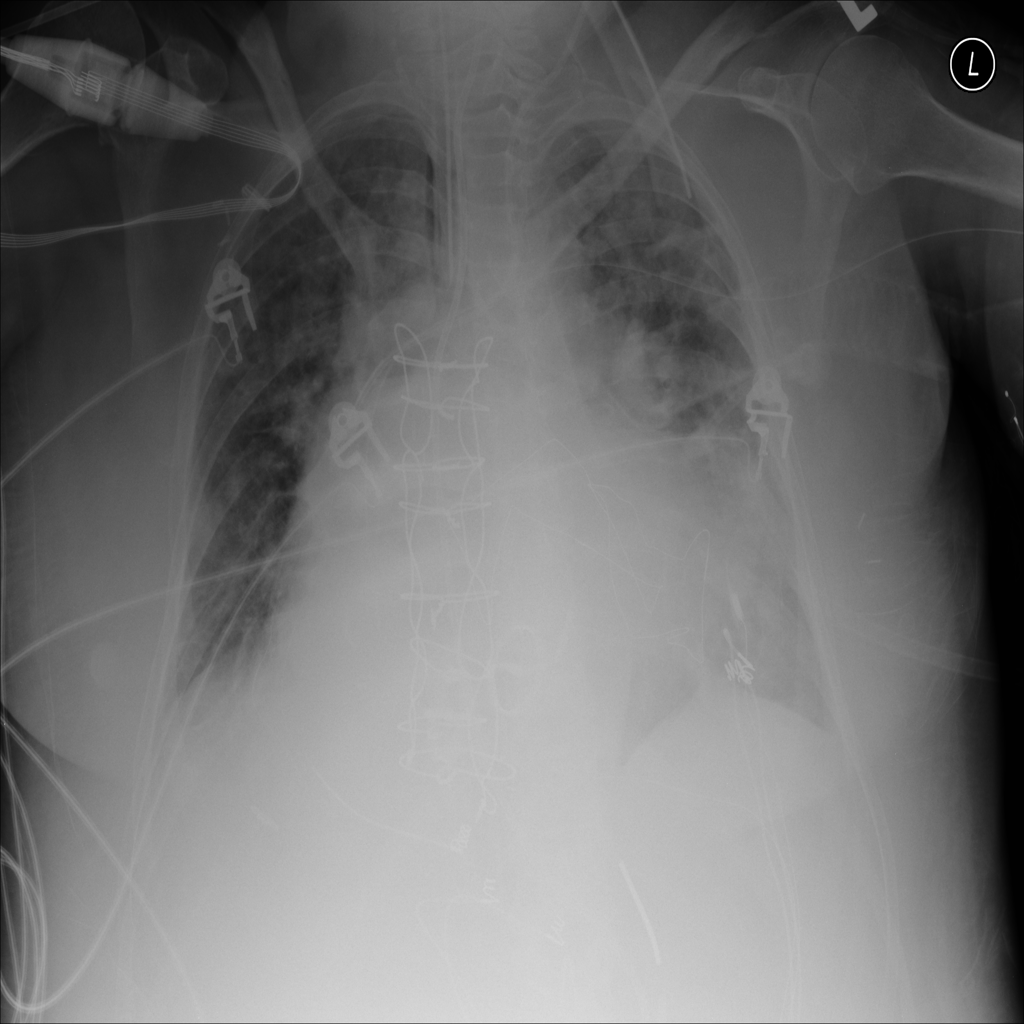

PAT-3384 · IMG-000Cardiomegaly

PAT-3384 · IMG-000

AP